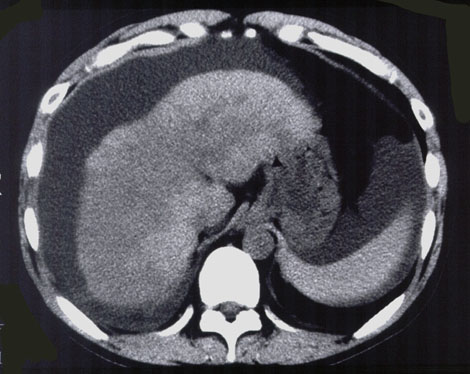

画像診断

肝萎縮,肝表面の不整,腹水,腹部超音波検査での地図状高エコー域(map sign),腹部CT検査での壊死部のCT値の低下などが認められます.

図.劇症肝炎の画像診断